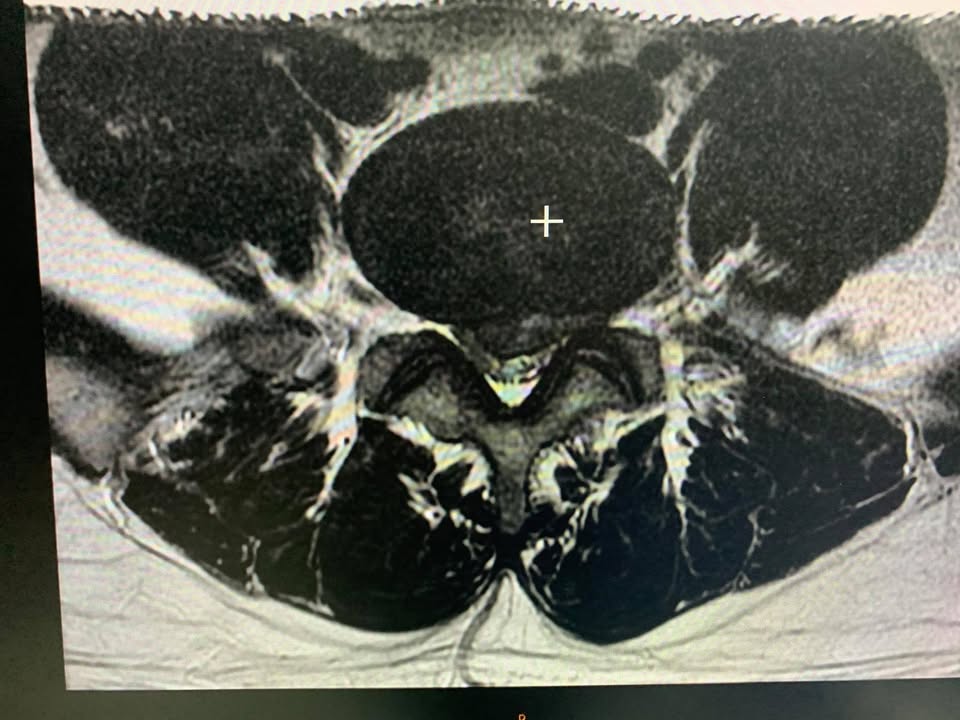

🔎多裂肌可以看到嗎?

可以的!透過核磁共振與肌肉骨骼超音波都看的到 ,在個案中發現駱先生多裂肌萎縮被脂肪組織白色部分填充